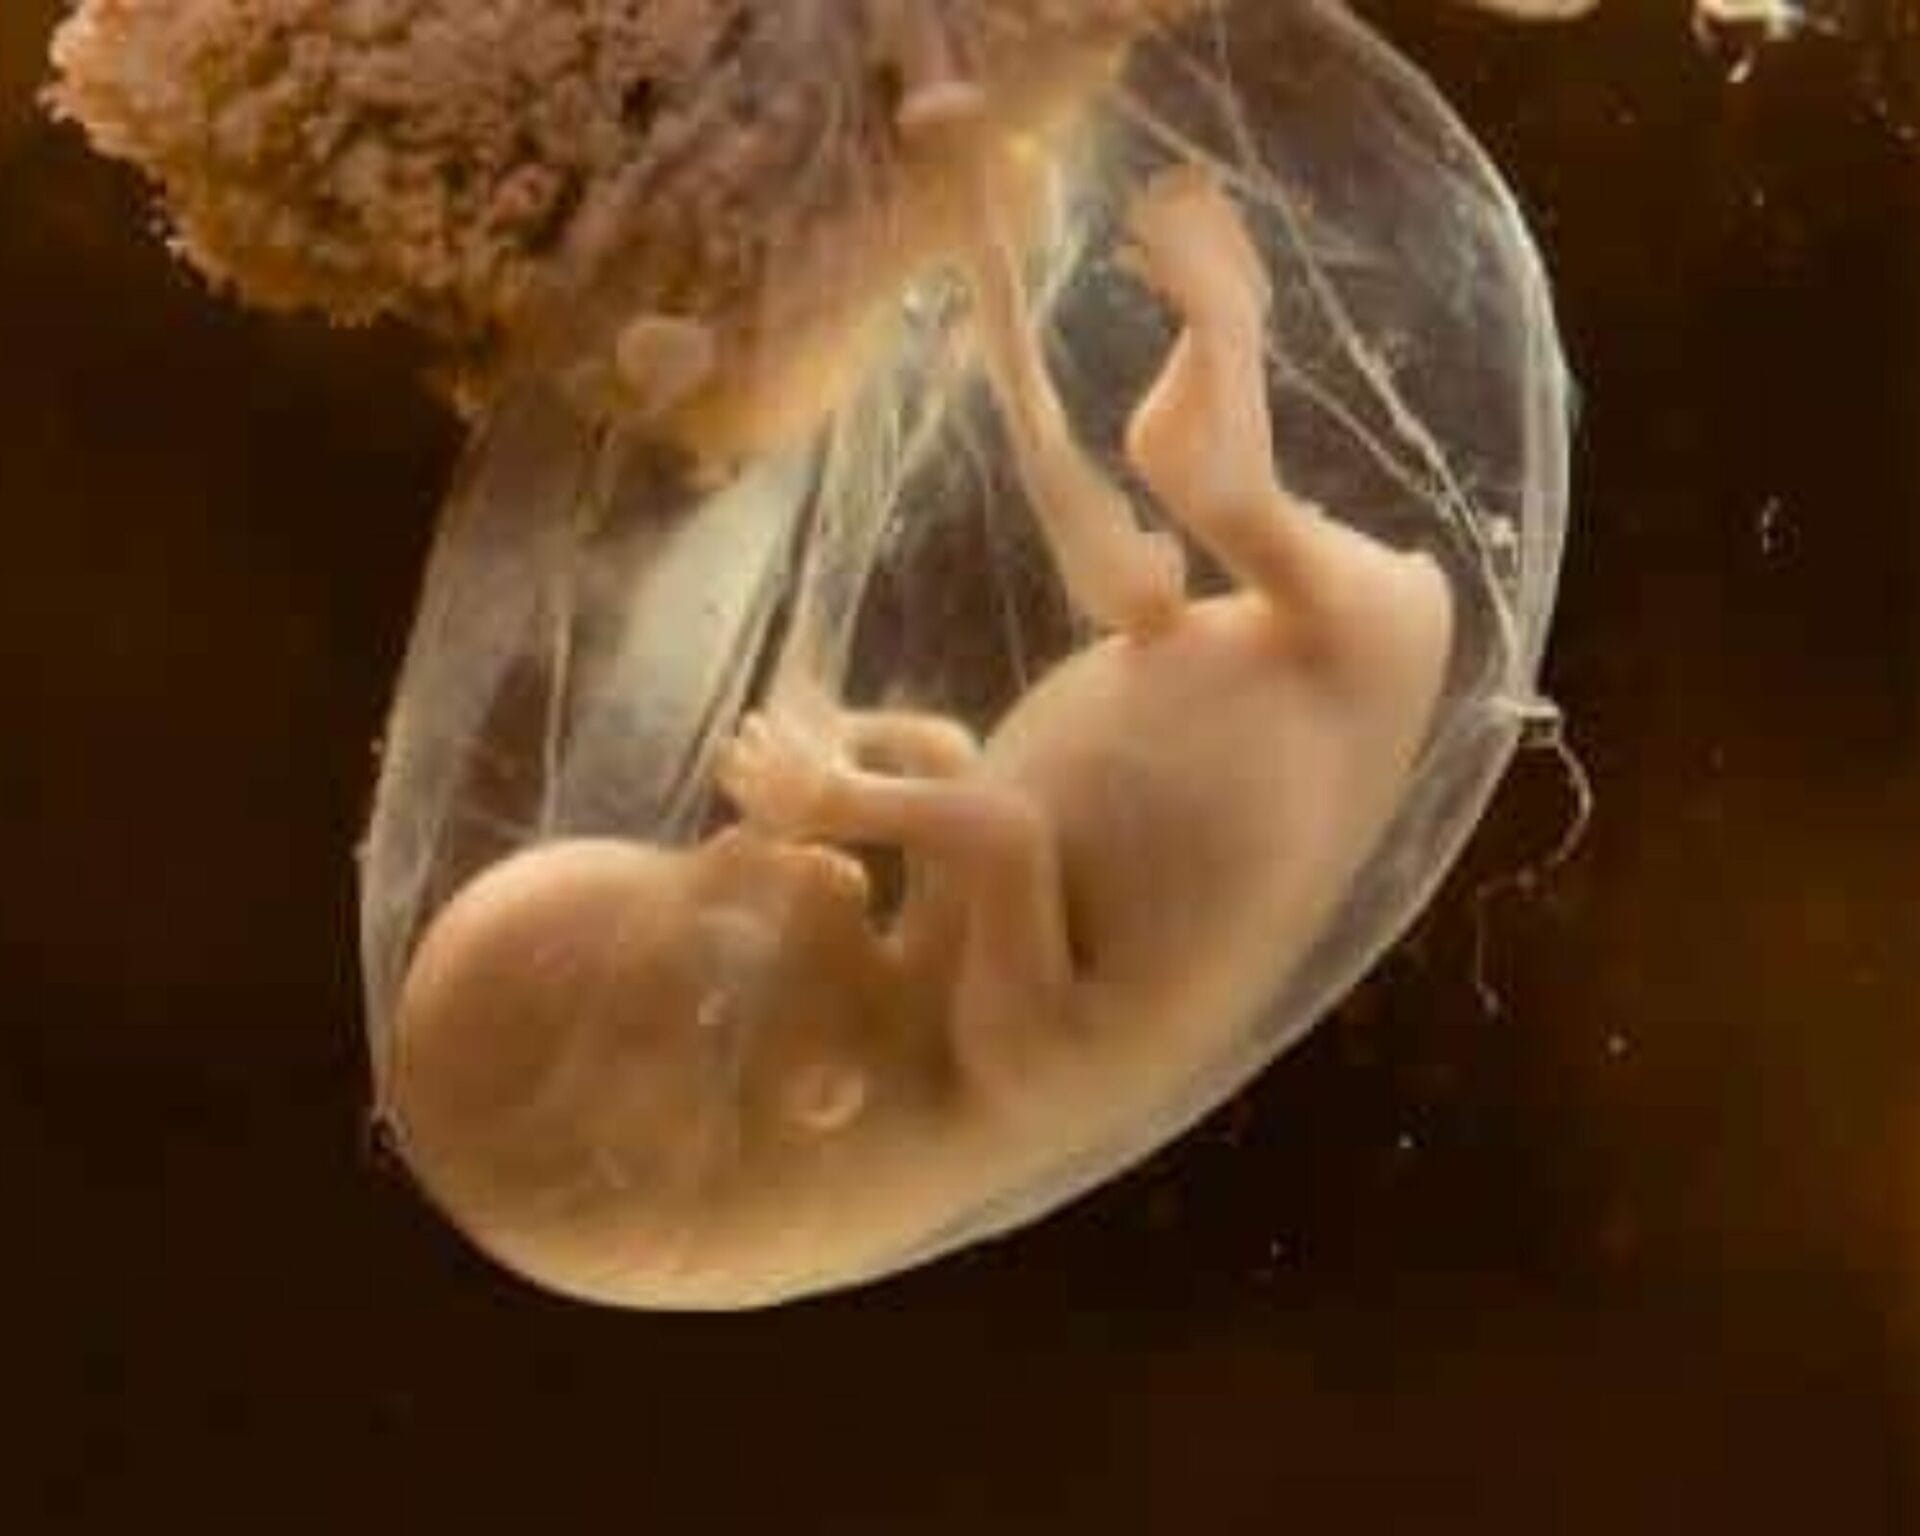

في الاسبوع الرابع والعشرين من الحمل يعتبر طفلك الأن قابلاً للحياة ولديه فرصة 50 في المائة للبقاء على قيد الحياة مع العناية المركزة إذا وُلد قبل أوانه – يرجع ذلك لأن جزء كبير منه وصل إلى التطوير النهائي لممرات الشعب الهوائية والحويصلات الهوائية في رئتيه.

زيادة في وزن الطفل تساعده حيث تعمل هذه الدهون على تخفيف التجاعيد من جسده – فهي تساعده على الاحتفاظ بحرارة الجسم وتنظيم درجة حرارته.

تنضج الآن رئتيه الصغيرتين حتى تتمكنان من استنشاق الهواء الفعلي بدلاً من السائل الأمنيوسي، يبدأ طفلك في إنتاج مادة خافضة للتوتر السطحي، وهو سائل مهم ضروري لطفلك للتنفس خارج الرحم، وفي الوقت نفسه تتشكل فروع رئتي طفلك، وكذلك الخلايا التي تنتج الفاعل بالسطح الرئوي: وهي مادة كيميائية تحدث بشكل طبيعي لتضخيم الأكياس الهوائية الصغيرة (وتسمى الحويصلات الهوائية) في رئتي طفلك عندما يكون مستعدًا للتنفس.

يصعب على الأطفال المولودين في وقت مبكر جدًا صعوبة في التنفس لأن هذه الخلايا إما لم تتطور تمامًا أو لا يمكنها إنتاج ما يكفي من الفاعل بالسطح الرئوي في هذا الأسبوع فلا يوجد هواء في رئتي الطفل، وتوجد فقط السائل الأمنيوسي، ولكن هذا لا يمنع طفلك من التنفس.